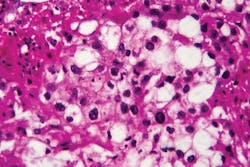

NCI’s Clinical Proteomic Tumor Analysis Consortium (CPTAC) is using a proteogenomic approach for tumor marker discovery for a growing number of cancers, including colorectal, breast, and ovarian cancers. By systematically identifying proteins (and associated biological processes) that originate from alterations in cancer genomes, CPTAC researchers have discovered new tumor subtypes, tumor microenvironment variations, and new potential proteins for targeted drug therapy. Recent innovations have suggested that these analyses could be done on a microscale using very small amounts of tumor tissue obtain from a biopsy.